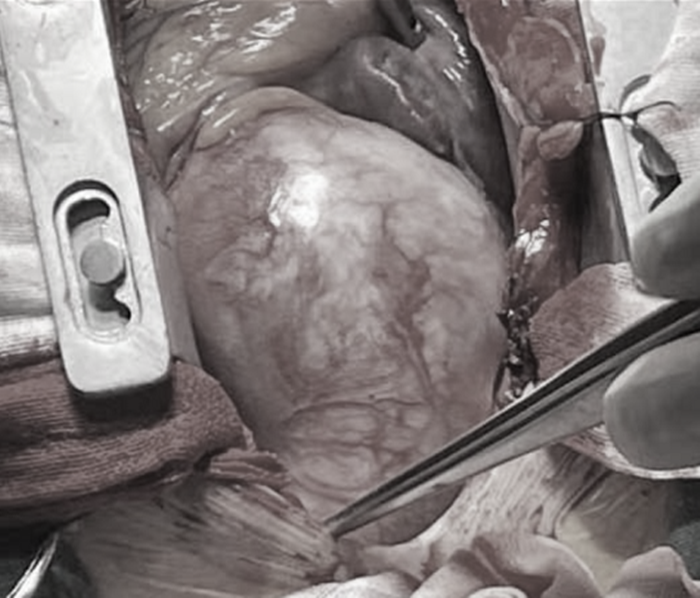

“David手術(shù)最大的特點(diǎn)就是保留患者的主動(dòng)脈瓣膜,經(jīng)過一段時(shí)間的休養(yǎng),就可以和正常人一樣生活,不需要終身服用抗凝藥物。”在周珉的帶領(lǐng)下,心胸外科團(tuán)隊(duì)為小吳順利實(shí)施David手術(shù),保留了主動(dòng)脈瓣,完成了主動(dòng)脈竇部再植。

手術(shù)前主動(dòng)脈情況

手術(shù)后主動(dòng)脈情況